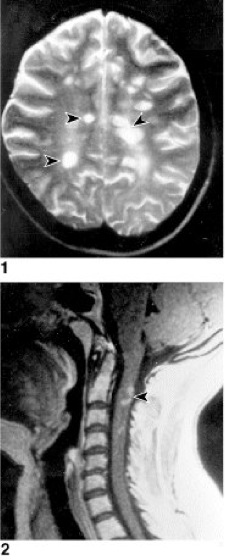

Kernspintomographische Aufnahmen von Entzündungsherden im 1 Gehirn und 2 Halsmark (klinisch Querschnittsmyelitis)

multiple Sklerosew [von *multiple , griech. sklēros = hart, steif], Encephalomyelitis disseminata, Abk. MS, degenerative Autoimmunerkrankung (Autoimmunkrankheiten) des Zentralnervensystems, die durch einen herdförmigen Zerfall der Myelinscheiden (Markscheide) gekennzeichnet ist. Auch die Nervenbahnen selbst werden zerstört. Die Erkrankung, als deren Ursache zeitweise auch eine „slow-virus“-Infektion (slow-Viren) diskutiert wurde, verläuft chronisch in zeitlich oft weit auseinanderliegenden Schüben, oft mit Rückbildungen der klinischen Symptomatik, kann aber auch langsam kontinuierlich progredient verlaufen. Die Symptome sind vielseitig – je nach dem Ausfall des jeweils befallenen Teils des Nervensystems, z.B. Sehstörungen, Doppelbilder durch Augenmuskellähmung, Zittern, Schwindelanfälle, Muskelschwäche, Lähmungen, Inkontinenz, Sensibilitäts- und Sprachstörungen, psychische Veränderungen. Die Erkrankung beginnt meist zwischen dem 20. und 40. Lebensjahr; Frauen erkranken häufiger als Männer. Die multiple Sklerose tritt nur in Nordeuropa und Nordamerika auf und ist mit einer Inzidenz von etwa 5 auf 100.000 Einwohner/Jahr in Mitteleuropa eine der häufigsten neurologischen Erkrankungen. Allein in Deutschland gibt es ca. 120.000 MS-Patienten. Bei 20% besteht eine familiäre Belastung. In den Entzündungsherden (Plaques) findet man u.a. T-Lymphocyten, B-Lymphocyten und Makrophagen, was als Hinweis auf eine Autoimmunreaktion gewertet werden kann. Es wurden Autoantikörper gegen verschiedene Komponenten der Myelinschicht nachgewiesen, so gegen die basischen Myelinproteine und die Proteolipid-Proteine (Proteolipide), aber auch gegen das Myelin-Oligodendrocyten-Glykoprotein (myelin oligodendrocyte glycoprotein, MOG). Der Anteil von MOG am Isoliermaterial ist zwar sehr gering, im Gegensatz zu den anderen Myelinbestandteilen kommt es aber nur im Zentralnervensystem vor. Außerdem scheint es an der Oberfläche der Myelinscheide zu sitzen und so für das Immunsystem besonders gut zugänglich zu sein. Da im Verlauf der Krankheit MOG-spezifische T-Zellen zuerst nachgewiesen werden, nimmt MOG vermutlich als Autoantigen bei der multiplen Sklerose eine Schlüsselstellung ein. Die Pathogenese der Erkrankung ist komplex, und etliche Erbanlagen wirken zusammen, welche die Empfindlichkeit für die Erkrankung erhöhen ( vgl. Infobox ). – Der empfindlichste Nachweis für die bei der multiplen Sklerose auftretenden Entzündungsherde ist die Kernspintomographie ( vgl. Abb. ). Neben Corticosteroiden (z.B. Cortison) zur Behandlung akuter Symptome werden neuerdings auch Immunglobuline eingesetzt. Offensichtlich reduzieren sie die Aktivität und Anzahl der gegen den eigenen Körper gerichteten T-Zellen, neutralisieren entzündungsfördernde Botenstoffe und sorgen dafür, daß einige der schädlichen Antikörper vernichtet werden. Eine Behandlung mit (rekombinant hergestelltem) Interferon β ist besonders bei schubförmigem Krankheitsverlauf (d.h., die Symptome treten in Schüben auf, zwischen denen sich der Zustand bessern kann) indiziert. Sowohl die Häufigkeit (um etwa 30%) als auch die Schwere der Schübe werden vermindert, in der Kernspintomographie sieht man kleinere Schadensareale im Gehirn. Die Schwere der durch die Krankheit auftretenden Behinderung ist aber wenig reduziert. Nach einer anfänglichen Euphorie mußte man erkennen, daß Patienten, die das Medikament 5 Jahre lang erhielten, offenbar nur in den ersten beiden Jahren davon profitierten. Eine Verbesserung bringt möglicherweise die Produktion von Interferon β in Säugerzellen, in denen das Protein wie das natürliche Interferon β glykosyliert (Glykosylierung) wird. Vermutlich hemmt Interferon β die krankheitsverstärkende Wirkung des in Lymphocyten gebildeten Interferons γ. Darüber hinaus kann mit Krankengymnastik, Massagen, Heilgymnastik u.a. dem Patienten Erleichterung verschafft und die drohende Invalidität hinausgezögert werden. Eine kurative Therapie ist nicht bekannt. In einem Tiermodell der multiplen Sklerose konnte ein therapeutischer Erfolg erzielt werden, indem man den Tieren das basische Myelin (als Antigen) über das Futter verabreichte. Dadurch werden supprimierende T-Zellen induziert, die, wie die Experimente weiter zeigten, durch den Tumor-Nekrosis-Faktor β (TNFβ) die autoreaktiven T-Zellen mit Spezifität für das basische Myelinprotein inhibieren. In der Beurteilung innovativer Behandlungsansätze der MS ist zu bedenken, daß eine Übertragung der tierexperimentellen Ergebnisse nur beschränkt möglich ist, da es sich bei der experimentellen allergischen Encephalomyelitis (EAE; vgl. Infobox ) um eine induzierte, im wesentlichen akut verlaufende Erkrankung handelt, während bei der chronisch verlaufenden MS akute entzündliche und demyelinisierende Läsionen parallel zu Reorganisationsvorgängen im zentralen Nervensystem ablaufen.